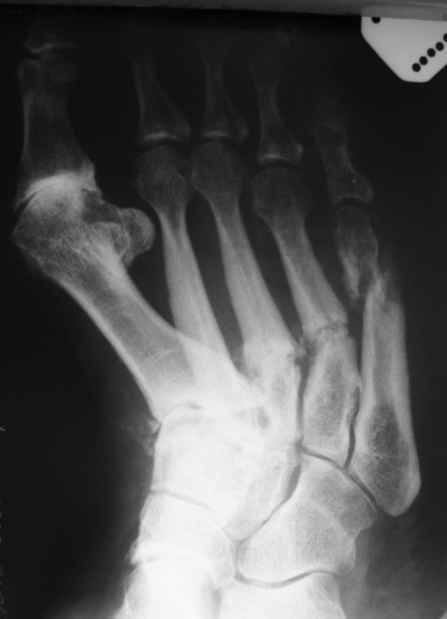

Уважаемые коллеги. Помогите определиться с дальнейшим лечением данного клинического случая (Ро - граммы прилагаю ).

Из анамнеза: Со слов больной травмы отрицает. Считает себя больной последние 5 лет, когда в первые появились боли в стопах и правом тазобедренном суставе. Обращалась в РТП по месту жительства, выполнялись Ро - граммы ( на руках ), без патологии. болевой синдром постепенно наростал. Пациентка лечилась консервативно по месту жительства с переменным успехом. Выполнялись этапные Ро - контроли ( к сожалению Ро - утерян в РТП ). Со слов пациентки Ро - картина ухудшалась. Данное ухудшение с февраля 2009 года. больная стала отмечать отрицательную динамику, появилось искривление области плюсны по тыльной поверхности стопы, крепитация отломков, усиление болевого синдрома, отёк в области правой стопы, формирование экзостоза головки 1 плюсневой кости, уплощения продольного свода стопы, невозможность носить ежедневной обуви ( в плоть до домашних тапочек ). и вот она измученная лечением обратилась к нам...Трудовой анамнез не отягощён. Работает поваром в столовой.Местно: У больной имеется отёк мягких тканей тыла стопы. при осмотре продольный и поперечный своды стопы уплощены. имеется вальгусная деформация 1 го пальца правой стопы. Экзостоз головки 1 плюсневой кости. Кожа над поверхностью не изменена. признаков гипертермии и гиперемии нет. При пальпации отмечается болезненность в проекции диафизов 2-4плюсневых костей по тыльной поверхности. Так же отмечается крепитация отломнов в проекции 5 плюсневой кости. Признаков сосудистых и неврологических расстройств нет. При стоянии на обеих ногах, отмечается болезненность в проекции 5 плюсневой кости правой стопы.

Looks as a Charcot-Peripheral neuropathy. Is she Diabetic? How old? A better X ray would be of help.-at least 2 projections. 1st TMT is involved. I am sure you can find some neuropathic changes at least in the other foot. Pes Cavus?

If no diabetes- Hypothyroidism, Vit B 12 deficiency, Spinal problem, Lepra, Amiodorone therapy,, Syphylis or HIV.

Действительно, не имея полного описания пациентки (вес, возраст, и прочие мелочи) о причине данных переломов можно строить различные догадки. Возможно, при детальном выяснении анамнеза, всплывёт какая-то незначительная травма (оступилась, неправильно поставила ногу), которая не акцентировала на себе внимание, но с учётом сопутствующих факторов, о которых многие говорят выше, произошла такая картина. Кстати как у пациентки с остеопорозом. По рентгенограмме признаки имеются, а проблемы в I плюстне-фаланговом суставе появились, как мне кажеться значительно раньше переломов (артроз практически III-IV стадии). Если будете проводить даообследование, интересно было-бы узнать конечный результат. Всем удачного месяца.

Как правильно заметил Михаил Васильев, нехватает некоторых мелочей. Пациентка В., возраст 45 лет. Вес 64,5 кг. Рост 168 см.

Мы так же как и доктор Кулешов установили диагноз стресс перелома или болезнь Дойчлендера. Пациента сейчас находится в гипсовой иммобилизации сроком уже 3 недели. До обращения к нам, пациентка лечилась по месту жительства без какой либо фиксации, нагружая ногу полностью.

Спасибо за предложения доктора Либерзона. дефицит витамина В 12 мы обязательно проверим, в остальном больная обследована на наличие всех инфекций.. - Отрицательно. Лечилась у невролога по месту жительства по поводу предполагаемого остеохондроза позвоночника ( ДО ВЫПОЛНЕНИЯ Ро грамм ),мы считаем, что снижение силы и рефлексов в нижних конечностях врядли пропустили. Сахарного диабета и заболеваний щитовидной железы нет. Уровень гормонов щитовидной железы в норме.

ещё фото боковая проекция правой стопы

Ро - левой стопы. последние 3 недели присоеделись боли. Если позволите Ро - находка!!!

Патологические переломы на обеих стопах...

И не большой вес у пациентки...

Явно какая то общая причина.

Нужно дифференцировать с mts, tbz,проблемами паращитовидных желез.Определите уровень кальция в крови.